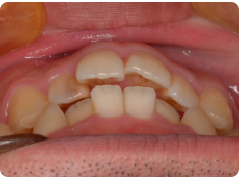

「上の前歯のデコボコを治したい」このような相談は、非常に多いです。

マウスピースで簡単に治せます。他院だと相場で1個につき20,000円前後。

当院は1個につき5,000円です。